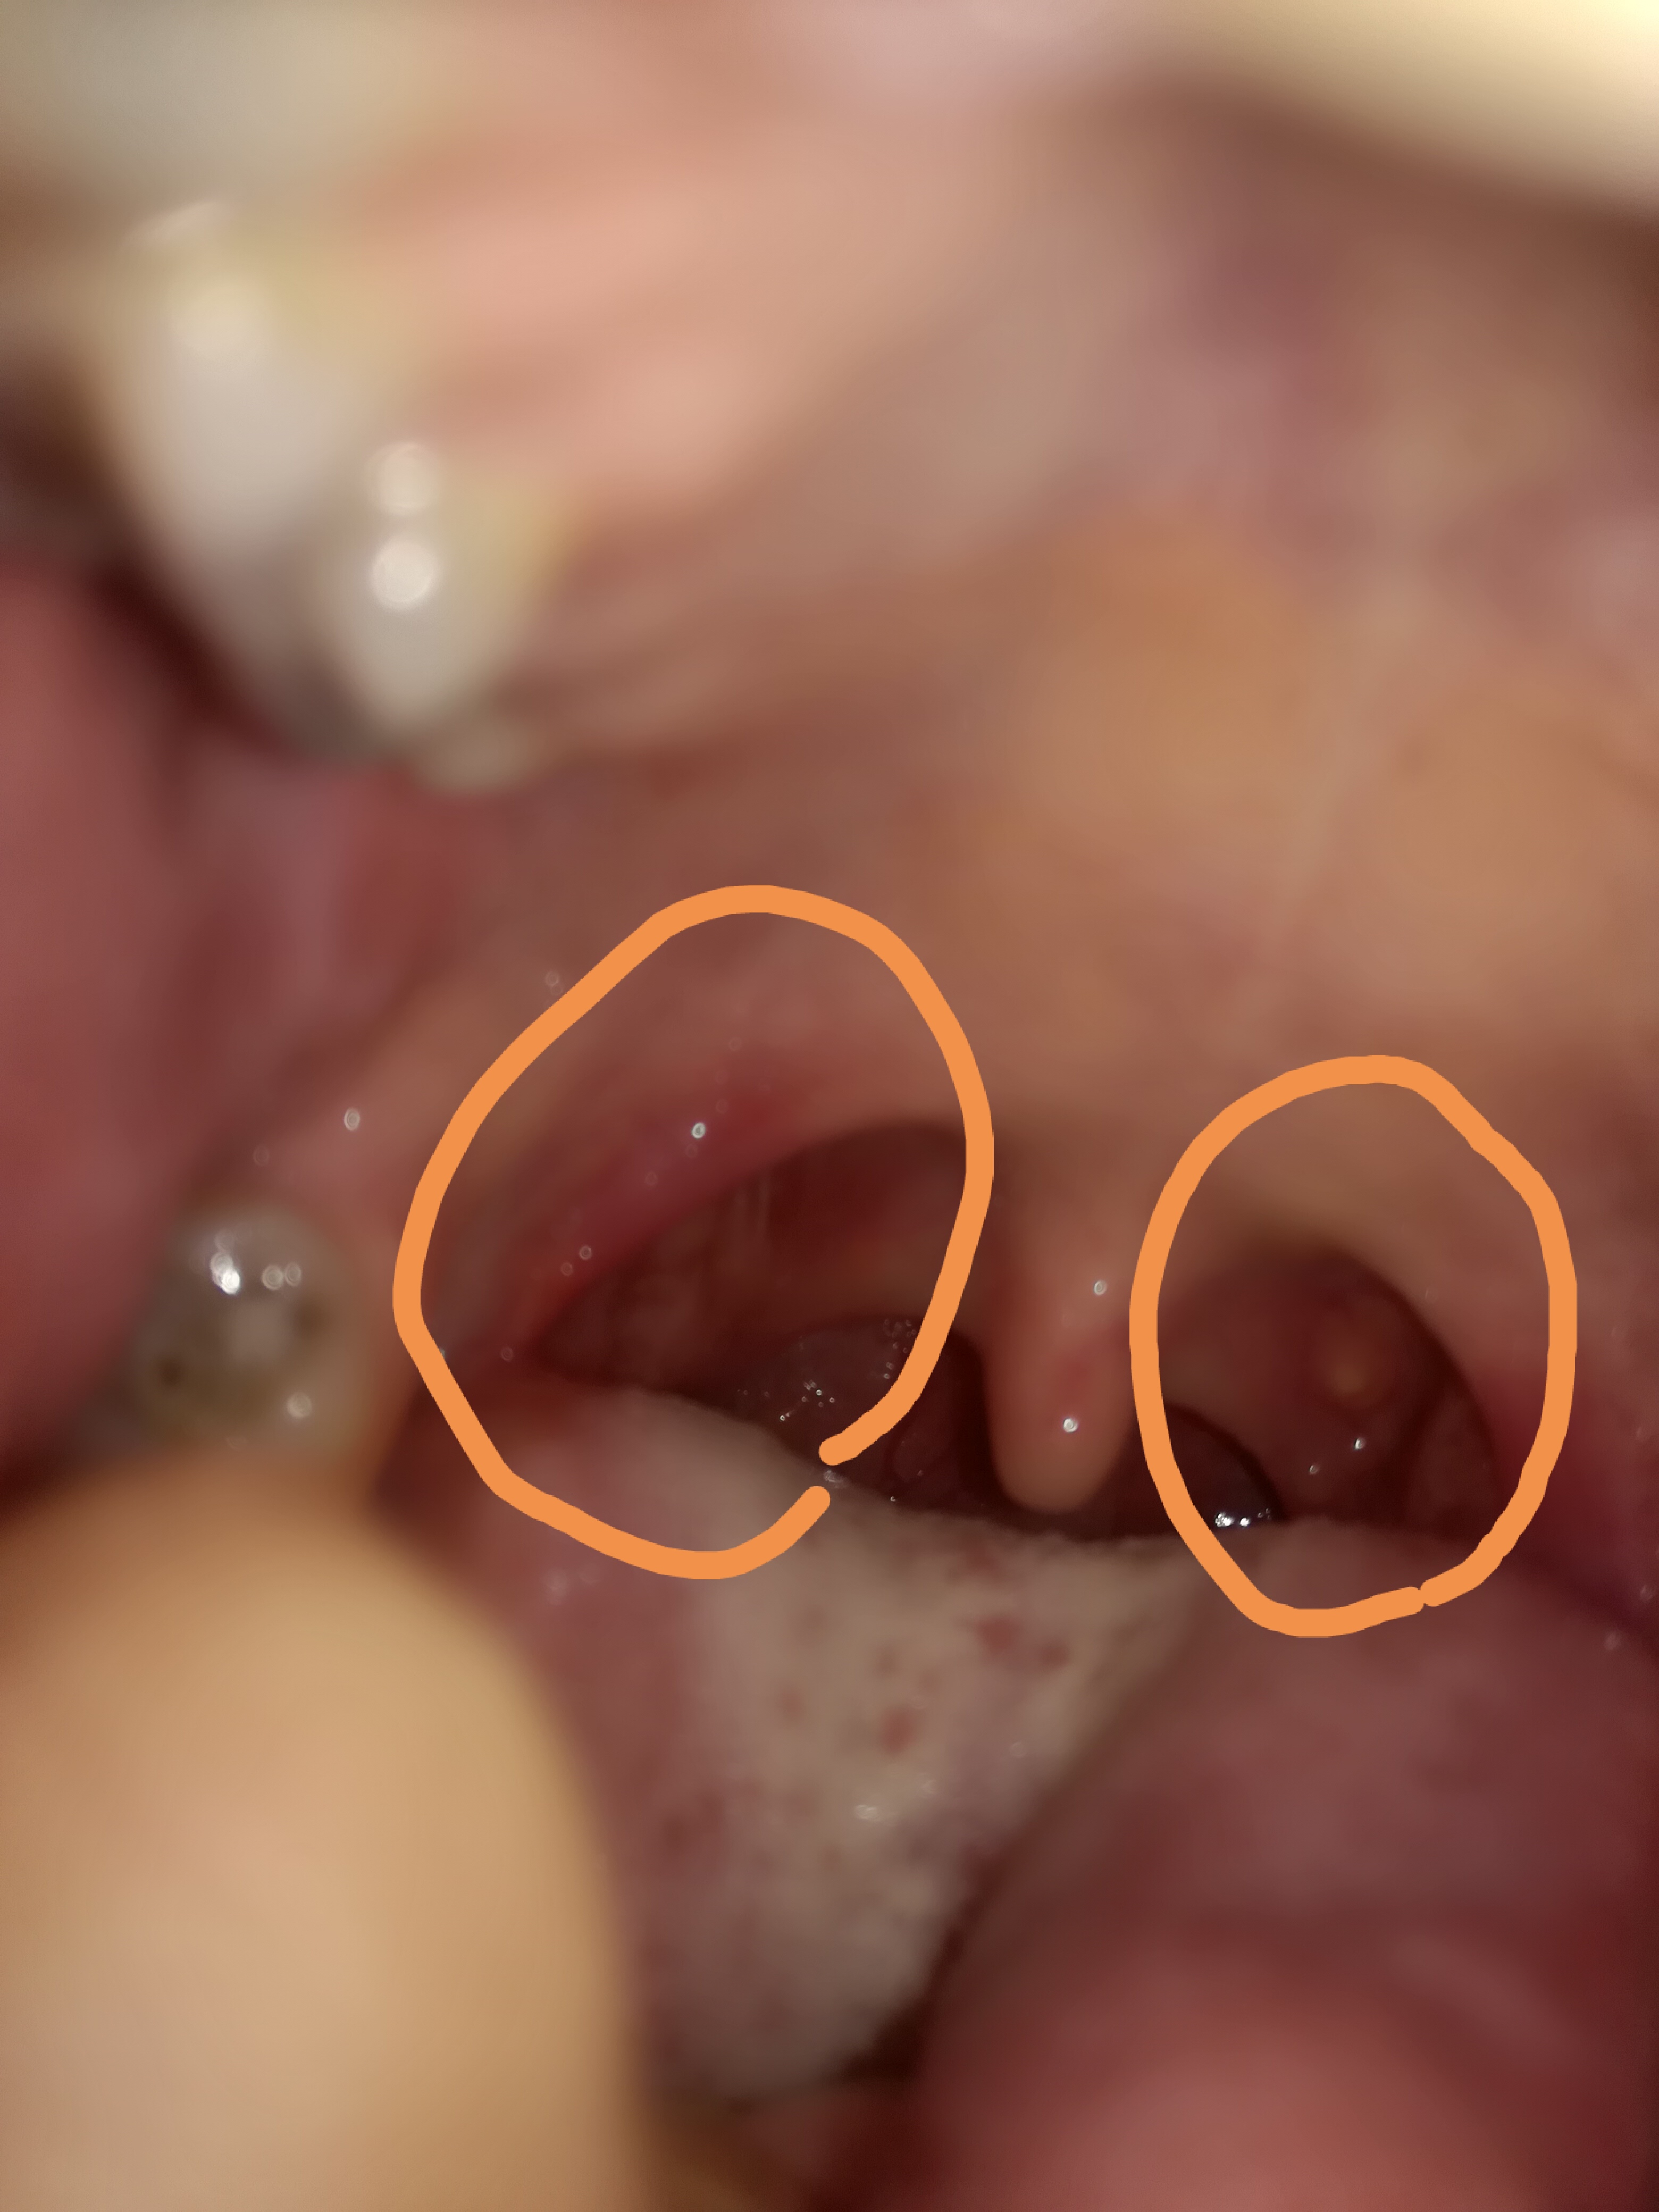

این برای منه سمت راست یه ،سمت چپ هم لوزمه یه چیزای سفید از سرخودش داره ؟

مطمعنی افته عزیزم؟ دکتر نرفتی؟ من افتایی ک میزنم معمولا قسمت داخلی لبم میزنه.تجربه مورد  اینچنینی نداشتم